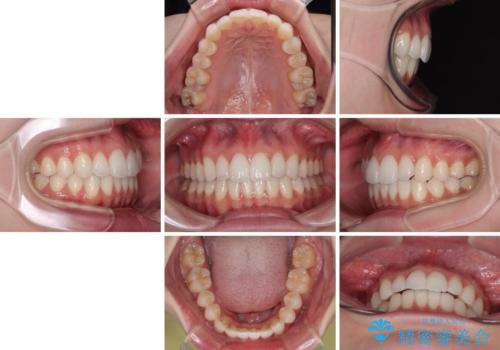

【モニター】前に傾斜した前歯 インビザラインでスッキリとした口元に

上下前歯の突出感とデコボコを気にして来院された患者様です。

インビザラインによる上下歯列の側方拡大と後方移動、必要に応じてIPR(歯と歯の間を削る)によりスペースの獲得により歯列を整えることとしました。

治療途中、出産や転居があり、2年ほど治療期間が長くなってしまいましたが、前歯の歯並びや飛び出した感覚を無事に改善させることができました。